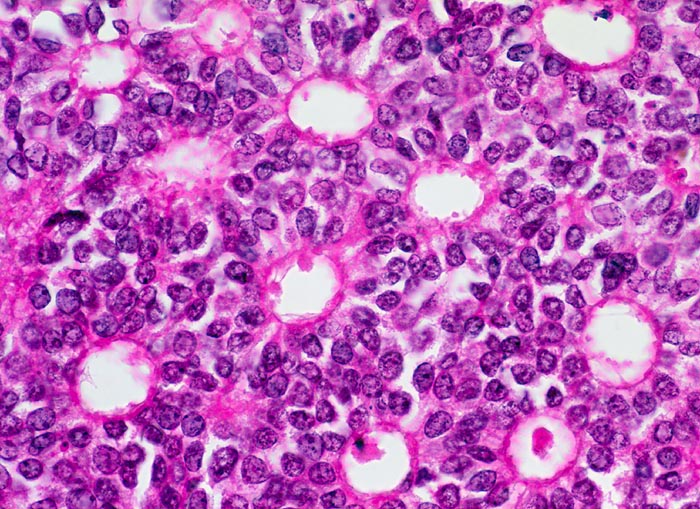

Das duktale Carcinoma in situ (DCIS) wird unterteilt in DCIS mit oder ohne Komedonekrosen. Das DCIS mit Komedonekrosen ist charakterisiert durch offensichtlich maligne Zellen auf nekrotischem Hintergrund. Zytologisch hochdifferenzierte DCIS ohne Komedonekrosen sind monomorpher.

Die individuellen Zellen eines duktalen Carcinoma in situ unterscheiden sich nicht von den Zellen eines invasiven dutkalen Karzinoms. DCIS sind im Gegensatz zum invasiven Karzinom gekennzeichnet durch einen stärkeren Zellzusammenhalt und grössere Uniformität der Verbände mit regelmässigen Abständen der Zellen und geringerem Zellcrowding. Makronukleolen sprechen für ein invasives Karzinom. Kleine Nukleolen hingegen können auch bei benignen Veränderungen auftreten.

Das DCIS zeigt im Gegensatz zur atypischen Hyperplasie eher diskohäsive Verbände und Einzelzellen. Bei der atypischen Hyperplasie sind gutartige Zellelemente beigemischt und die Verbände können irreguläre oder schlitzartige Lumina enthalten.

Unten werden Beispiele von einem zytologisch hochdifferenzierten und einem zytologsich wenig differenzierten DCIS mit Komedonekrosen gezeigt.